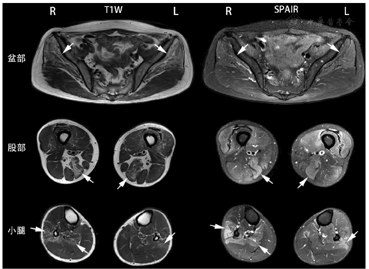

Spectral Attenuated Inversion Recovery(SPAIR):频率衰减反转恢复序列

入院后查肌酸激酶137 U/L,甲状腺功能、风湿相关指标、肝肾功、肿瘤标记物、HIV抗体均未见明显异常。血清球蛋白水平43.7 g/L(20~40 g/L),进一步行血清免疫固定电泳提示游离λ轻链阳性。骨髓穿刺细胞学:浆细胞占1%,形态大致正常。骨髓流式细胞学:未见异常浆细胞。全身骨质X线片亦未见明显溶骨或破骨性表现。心脏超声及肺功能均未见明显异常。肌电图提示肌源性损害,可见纤颤及正锐波。肌肉MRI结果示双侧臀中肌、臀小肌、半膜肌、腓骨肌群及右侧比目鱼肌受累(图1 )。右肱二头肌活检,病理显示肌纤维大小明显不等,核袋易见(图2A),萎缩的肌纤维内泥沙样物质沉积,合并细小空泡形成(图2B),Z盘蛋白α-actinin免疫组化染色呈阳性(图2C),κ及λ轻链染色均阴性。电镜可见肌纤维内典型的杆状体形成,与Z盘相关(图2D)。

SLONM的经典临床表现为亚急性或慢性进展的、不对称的四肢近端为著的肌肉无力及萎缩,可伴或不伴有球部症状。半数以上的患者可因颈伸肌无力出现"垂头"表现[8],少数患者可以孤立性的"垂头"起病。慢性的心肺功能受累可使患者并无明显胸闷、憋喘等症状,需引起临床医师的关注[8]。肌电图常表现为肌源性或混合性损害伴自发电位,而大部分患者的肌酸激酶正常或仅轻度升高[11],此点不同于肌炎或肌营养不良等常见的坏死性肌病。有研究发现,SLONM的肌肉MRI常选择性地累及颈伸肌、椎旁肌、臀小肌和臀中肌,腘绳肌、比目鱼肌,可与其他类似的肌病进行鉴别。本例患者并无颈伸肌和球部肌受累,心肺功能亦无明显异常,但四肢肌无力的分布、电生理和肌肉MRI的表现均与既往报道的经典表现一致,具有一定的代表性。